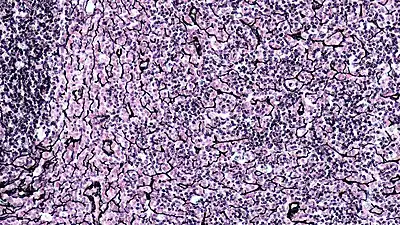

Ретикулярная ткань

Ретикуля́рная ткань (лат. textus reticularis) — особая форма соединительной ткани[1], состоящая из так называемых ретикулярных волокон и формирующих их ретикулярных клеток. Ретикулярная ткань образует строму кроветворных органов и формирует микроокружение для клеток крови, формирующихся в них[2], однако обнаруживается и в органах, не связанных с кроветворением.